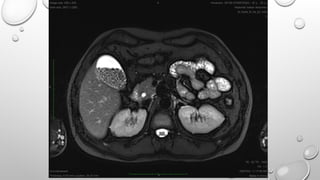

• THESE SEQUENCES ARE USED FOR 2D AND VOLUME ACQUISTIONS TO OBTAIN T1 WEIGHTED

BREATH HOLD IMAGES AS TR IS SHORT. THESE ALSO DEMONSTRATE GOOD T1 ANATOMY AND

PATHOLOGY AFTER GADOLINIUM CONTRAST.

• AS STIMULATEDECHO CONTAINS MAINLY T2 AND T2* INFORMATION AND THIS IS SPOILED , THESE SEQUENCES PRODUCE T1 IMAGES. THIS IS BECAUSE IMAGE CONTRAST IS MAINLY INFLUNCED BY FID THAT CONTRIBUTES T1 CONTRAST. • THESE SEQUENCES ARE USED FOR 2D AND VOLUME ACQUISTIONS TO OBTAIN T1 WEIGHTED BREATH HOLD IMAGES AS TR IS SHORT. THESE ALSO DEMONSTRATE GOOD T1 ANATOMY AND PATHOLOGY AFTER GADOLINIUM CONTRAST. SIEMENS SEQUENCES FLASH MODIFICATION MEDIC MP RAGE IN PHASE OUT OF PHASE IMAGING